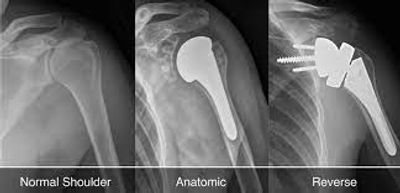

Shoulder Replacement surgery wherein all or part of the glenohumeral joint is supplanted by a prosthetic implant. If your shoulder joint gets genuinely harmed, you may require medical procedure to replace it.

During the medical procedure, specialists supplant the harmed joint "ball," known as the humeral head, of the shoulder with a metal ball. They likewise place a plastic surface on the "socket" of the shoulder, known as the glenoid.

Now and then, a partial shoulder replacement can be performed. This includes replacing just the ball of the joint.

There are various sorts of shoulder substitutions that are done. Your specialist will assess your circumstance cautiously before settling on any choices.

The typical shoulder replacement includes supplanting the ligament joint surfaces with an exceptionally cleaned metal ball connected to a stem, and a plastic socket.

Contingent upon the state of your shoulder, your specialist may supplant just the ball. This method is known as a hemiarthroplasty. In a traditional hemiarthroplasty, the head of the humerus is supplanted with a metal ball and stem, like the segment utilized in a total shoulder substitution. This is known as a stemmed hemiarthroplasty.

Resurfacing hemiarthroplasty includes supplanting only the joint surface of the humeral head with a top like prosthesis without a stem. With its bone safeguarding advantage, it offers those with joint inflammation of the shoulder an option in contrast to the standard stemmed shoulder substitution.

Another kind of shoulder substitution is called reverse absolute shoulder substitution. It is used for people who have: